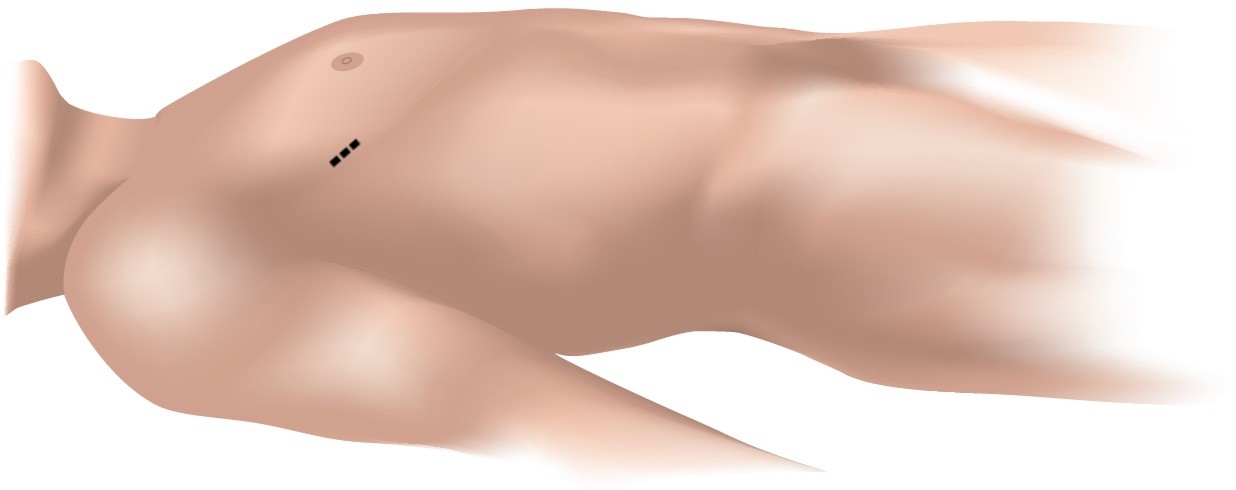

Patients with isolated mitral valve disease may be candidates for minimally invasive surgery, so long as they do not have clinically relevant aortic valve disease or coronary artery disease. Surgeons perform the operation by making only a small 4-6 cm incision on the right side of the chest instead of the large midline-incision and division of the sternum used traditional open surgery.

| Small, 4-6 cm Incision on the Right Side of The Chest |